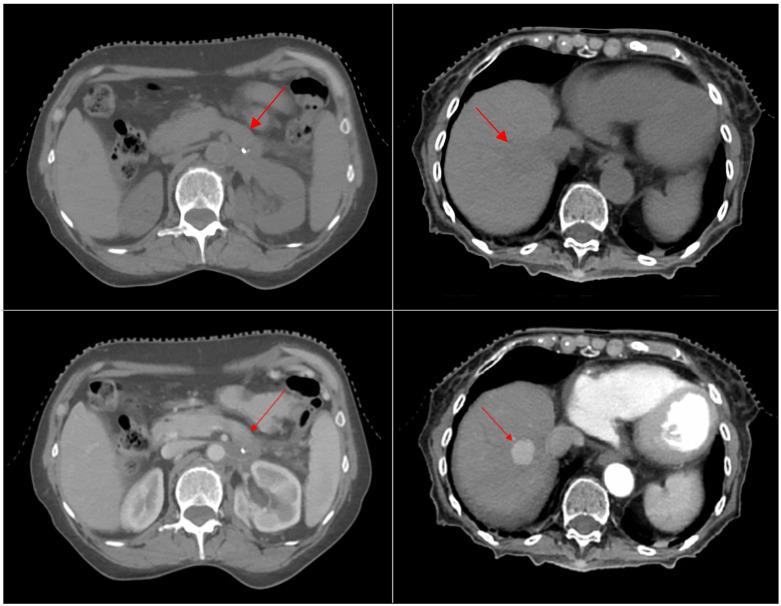

To present the technical aspects of contrast-enhanced 4DCT (ce4DCT) simulation for abdominal SBRT. Twenty-two patients underwent two sequential 4DCT scans: one baseline and one contrast-enhanced with personalized delay time () calculated to capture the tumor in the desired contrast phase, based on diagnostic triple-phase CT. The internal target volume (ITV) was delineated on ten contrast phases, and a panel of three experts qualitatively evaluated tumor visibility. Aortic HU values were measured to refine the for subsequent patients. The commonly used approach of combining triple-phase CT with unenhanced 4DCT was simulated, and differences in target delineation were evaluated by volume, centroid shift, Dice and Jaccard indices, and mean distance agreement (MDA). The margins required to account for motion were calculated. The ce4DCT acquisitions substantially improved tumor visibility over the entire breathing cycle in 20 patients, according to the experts' unanimous evaluation. The median contrast peak time was 54.5 s, and the washout plateau was observed at 70.3 s, with mean peak and plateau HU values of 292 ± 59 and 169 ± 25. The volumes from the commonly used procedure (ITV2) were significantly smaller than the ce4DCT volumes (ITV1) ( = 0.045). The median centroid shift was 4.7 mm. The ITV1-ITV2 overlap was 69% (Dice index), 53% (Jaccard index), and 2.89 mm (MDA), with the liver volumes showing significantly lower indices compared to the pancreatic volumes ( ≤ 0.011). The margins required to better encompass ITV1 were highly variable, with mean values ≥ 4 mm in all directions except for the left-right axis. The ce4DCT simulation was feasible, resulting in optimal tumor enhancement with minimal resource investment, while significantly mitigating uncertainties in SBRT planning by addressing poor visibility and respiratory motion. Triple-phase 3DCT with unenhanced 4DCT led to high variability in target delineation, making the isotropic margins ineffective.

介绍腹部立体定向体部放疗(SBRT)的对比增强4DCT(ce4DCT)模拟的技术方面。22例患者接受了两次连续的4DCT扫描:一次为基线扫描,一次为对比增强扫描,根据诊断性三相CT计算个性化延迟时间(),以在所需的对比期捕获肿瘤。在十个对比期勾画内部靶区(ITV),由三名专家组成的小组对肿瘤可视性进行定性评估。测量主动脉HU值以优化后续患者的。模拟了将三相CT与非增强4DCT相结合的常用方法,并通过体积、质心移位、Dice和Jaccard指数以及平均距离一致性(MDA)评估靶区勾画的差异。计算了考虑运动所需的边界。根据专家的一致评估,ce4DCT采集在20例患者的整个呼吸周期中显著提高了肿瘤可视性。对比峰值时间中位数为54.5秒,在70.3秒观察到洗脱平台期,平均峰值和平台期HU值分别为292±59和169±25。常用方法(ITV2)的体积明显小于ce4DCT体积(ITV1)(=0.045)。质心移位中位数为4.7毫米。ITV1与ITV2的重叠率为69%(Dice指数)、53%(Jaccard指数)和2.89毫米(MDA),肝脏体积的各项指数明显低于胰腺体积(≤0.011)。更好地包围ITV1所需的边界高度可变,除左右轴外,所有方向的平均值≥4毫米。ce4DCT模拟是可行的,以最小的资源投入实现了最佳的肿瘤增强,同时通过解决可视性差和呼吸运动问题,显著降低了SBRT计划中的不确定性。三相3DCT与非增强4DCT导致靶区勾画的高度变异性,使得各向同性边界无效。